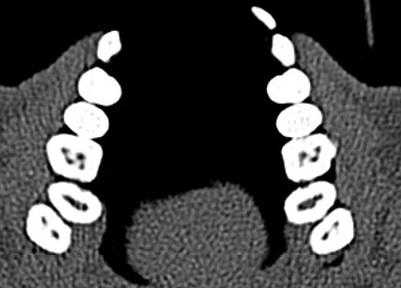

Выявлено, что у зубов с необтурированными КК при использовании распространенной в эндодонтической практике внутриротовой периапикальной рентгенографии, как правило, невозможно отчетливо визуализировать в каждом корне более 1 КК. В большинстве случаев это происходит из-за суммирования теней КК в каждом корне зуба (рис. 1, а; 2, а). В зоне нижней трети корней зубов отображение КК становилось нечетким либо вообще отсутствовало. При рентгенографии параллельной техникой изображение корней зубов было более качественным, чем при периапикальной съемке, но имело аналогичные закономерности (см. рис. 1, б). Использование для раздельной визуализации КК периапикальной рентгенографии в косой проекции приводило к ухудшению изображения нижних отделов корней всех групп зубов. На ОПМН КК зубов визуализировались недостаточно отчетливо (см. рис. 1, в).

Рис. 1. Исследование первого моляра верхней челюсти в эксперименте. При внутриротовой периапикальной рентгенографии (а), рентгенографии, выполненной параллельной техникой (б), в мезиальном щечном корне виден 1 КК; на фрагменте ОПМГ КК различаются нечетко (в); при КЛКТ на аксиальных срезах выявляются в мезиальном щечном корне 2 КК (г) и апикальные отверстия в дистальном щечном корне (д), на косом срезе определяется расположение корневых каналов (е).

Рис. 2. Исследование зуба 3.6. На внутриротовой периапикальной рентгенограмме (а) создается картина наличия только 1 канала в каждом из корней зуба; по данным аксиального среза КТ (б) отчетливо визуализируются по 2 КК в каждом из корней.

Рентгеновская КТ с построением аксиальных и косых срезов (см. рис. 1, г, д, е; 2, б) в сравнении с внутриротовой рентгенографией предоставляла объективные сведения о строении корней всех групп зубов. Информация о строении корней зубов, полученная при КТ перед эндодонтическими манипуляциями, позволяла заранее спланировать рациональную тактику лечения. В процессе эндодонтического лечения данные КТ способствовали сокращению времени на выявление устьев КК и повышению качества эндодонтического лечения.